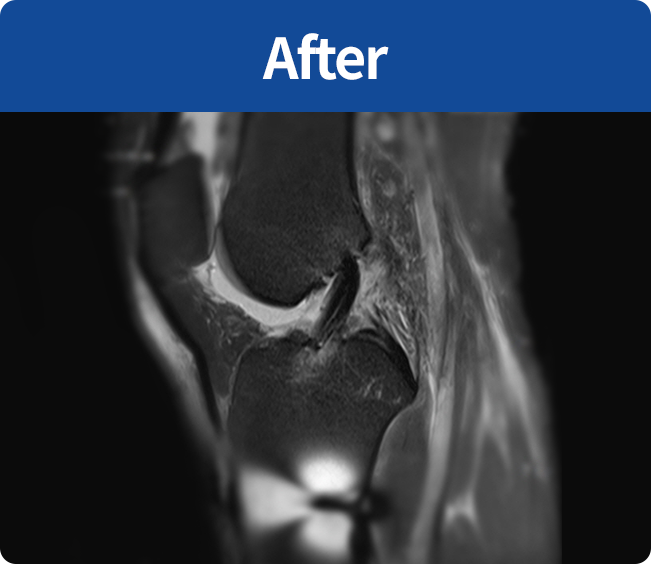

십자인대 재건술

무릎의 십자인대 손상에 자가 아킬레스건이나

동종(인공)인대를 사용하여 손상된 인대를

대체하게 하여 기능을 재건하는 수술법

(전방십자인대, 후방십자인대)

무릎의 십자인대 손상에 자가 아킬레스건이나 동종(인공)인대를 사용하여

손상된 인대를 대체하게 하여 기능을 재건하는 수술법(전방십자인대, 후방십자인대)